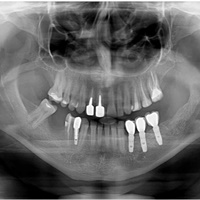

Odbudowa kosci wyrostka zębodołowego żuchwy, odbudowa dziąsła, wydłużenie koron klinicznych górnych przedtrzonowców, implantacja.

Po zabiegu transplantacji zęba rozwinęła się resorbcja i trzeba było usunąć ząb. Zdjęcia po dobudowie kosci, implantacji i leczeniu protetycznym.

Zabiegi regeneracyjne są dość popularne. Tutaj jednoczasowa augmentacja pionowa dowierzchołkowo i dokoronowo, oraz augmantacja pozioma.